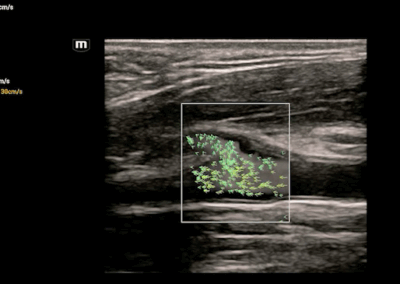

Consona N6

El Consona presenta soluciones nuevas y concretas, que lo ayudarán a realizar diagnósticos fluidos para amplios tipos de pacientes de manera eficaz.

No importa que su rutina sea en hospitales, clínicas, o que esté perfeccionando sus habilidades, en esta serie encontrará herramientas muy potentes y disponibles para mantenerse a la vanguardia.

Consona N7

El Consona presenta soluciones nuevas y concretas, que lo ayudarán a realizar diagnósticos fluidos para amplios tipos de pacientes de manera eficaz.

No importa que su rutina sea en hospitales, clínicas, o que esté perfeccionando sus habilidades, en esta serie encontrará herramientas muy potentes y disponibles para mantenerse a la vanguardia.

Consona N9

El Consona presenta soluciones nuevas y concretas, que lo ayudarán a realizar diagnósticos fluidos para amplios tipos de pacientes de manera eficaz.

No importa que su rutina sea en hospitales, clínicas, o que esté perfeccionando sus habilidades, en esta serie encontrará herramientas muy potentes y disponibles para mantenerse a la vanguardia.